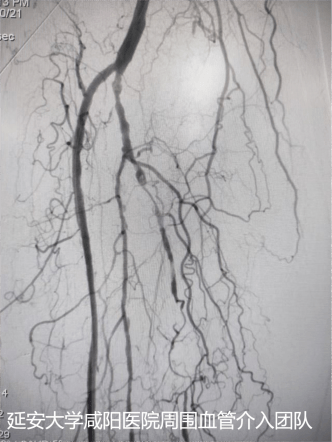

術后DSA